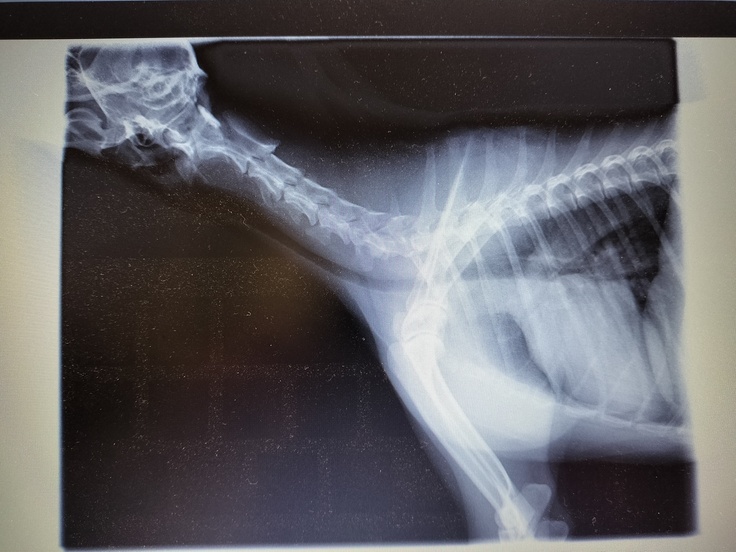

15日昼に退院。先生からの詳しい説明を頂きました。やはりかなり気管は潰れていてステージⅣだったそうです。

レントゲン写真でも潰れていた気管が丸くなったのがよくわかります。感動しました。

↑左が術後、右が術前です。綺麗な丸になっています。

↑左が術前右が術後です。

↑一番ひどい部分はほとんど 潰れており よく これだけの咳で収まっていたな と言われました。